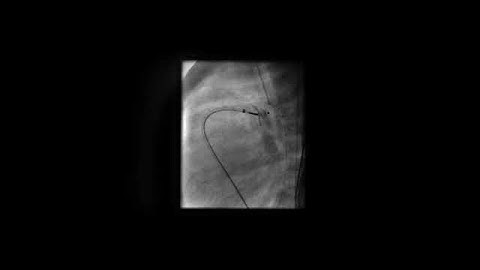

PDA device closure Exposure of the PA end of the device